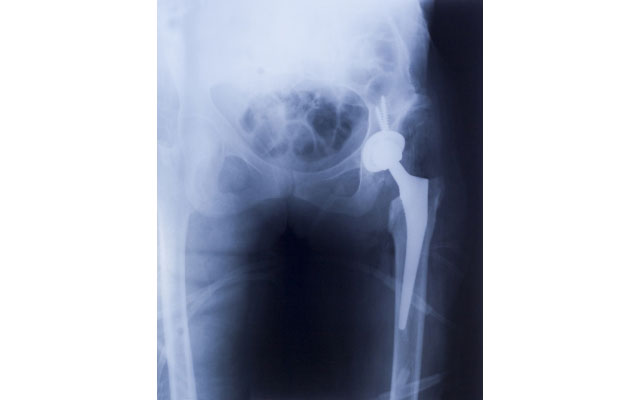

「羅先生的髖關節表面花白了,原本應該是球形的關節表面,部分因沒血流到而嚴重損毀,出現缺血性骨枯,令他郁動時出現骨磨骨的情況,故出現劇痛。」鄧醫生說。由於髖關節出現骨枯嚴重影響羅先生的活動能力,要徹底解決問題,擺在面前的只有手術治療,將壞關節及骨枯部分切走,換一個人工關節。手術以外,其他方法都只能治標,不能治本。因應羅先生的情況,鄧醫生認為他適合換一種新型的「表面髖關節」,效果較傳統的「全髖關節置換」更優勝。「表面髖關節置換的好處,第一是差不多可以完全複製病人『股骨頭』出來,在力學及活動能力較全髖關節更佳;第二個好處是置放好後,脫位機會較微。」鄧醫生說。

此外,全髖關節置換,需要切走的骨骼較多,「首先要割走整個股骨頭,然後再於股骨近端用鋤鋤走骨骼,才可以放入一支長七至八吋的金屬柄。但好多時出問題的,只是關節表面,即關節的『骹位』磨蝕,如果因關節表面出現問題而要切走這些骨,會令病人損失很多健康的骨頭。」鄧醫生說。故此這個表面髖就是針對此問題,保留病人本身正常骨組織,只需將表面損毀部分磨走,然後安裝一個人造關節面,對面髖骨亦同樣安裝一個人造關節面,像帽子般起着保護作用,包護上下兩邊的骨。